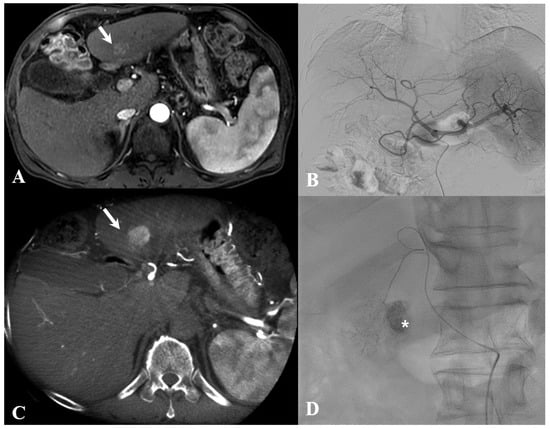

Figure 6. A 54-year-old man with a single hepatocellular carcinoma. (A) Arterial phase of a magnetic resonance imaging (MRI) scan demonstrates a hypervascular mass (white arrow) in segment 3 of the liver. (B) Arterial phase of celiac angiography does not show a small hypervascular tumor. (C). Cone-beam computed tomography (CBCT) increases sensitivity for detecting hypervascular tumor (white arrow), which is hard to see using digital subtraction angiography (DSA). (D) Successful transcatheter arterial chemoembolization (TACE) is performed after advanced applications (EmboGuide, Philips, Healthcare, Best, the Netherlands) providing three-dimensional vessel navigation for superselection. Note the treated lesion with good lipiodol uptake (asterisk).